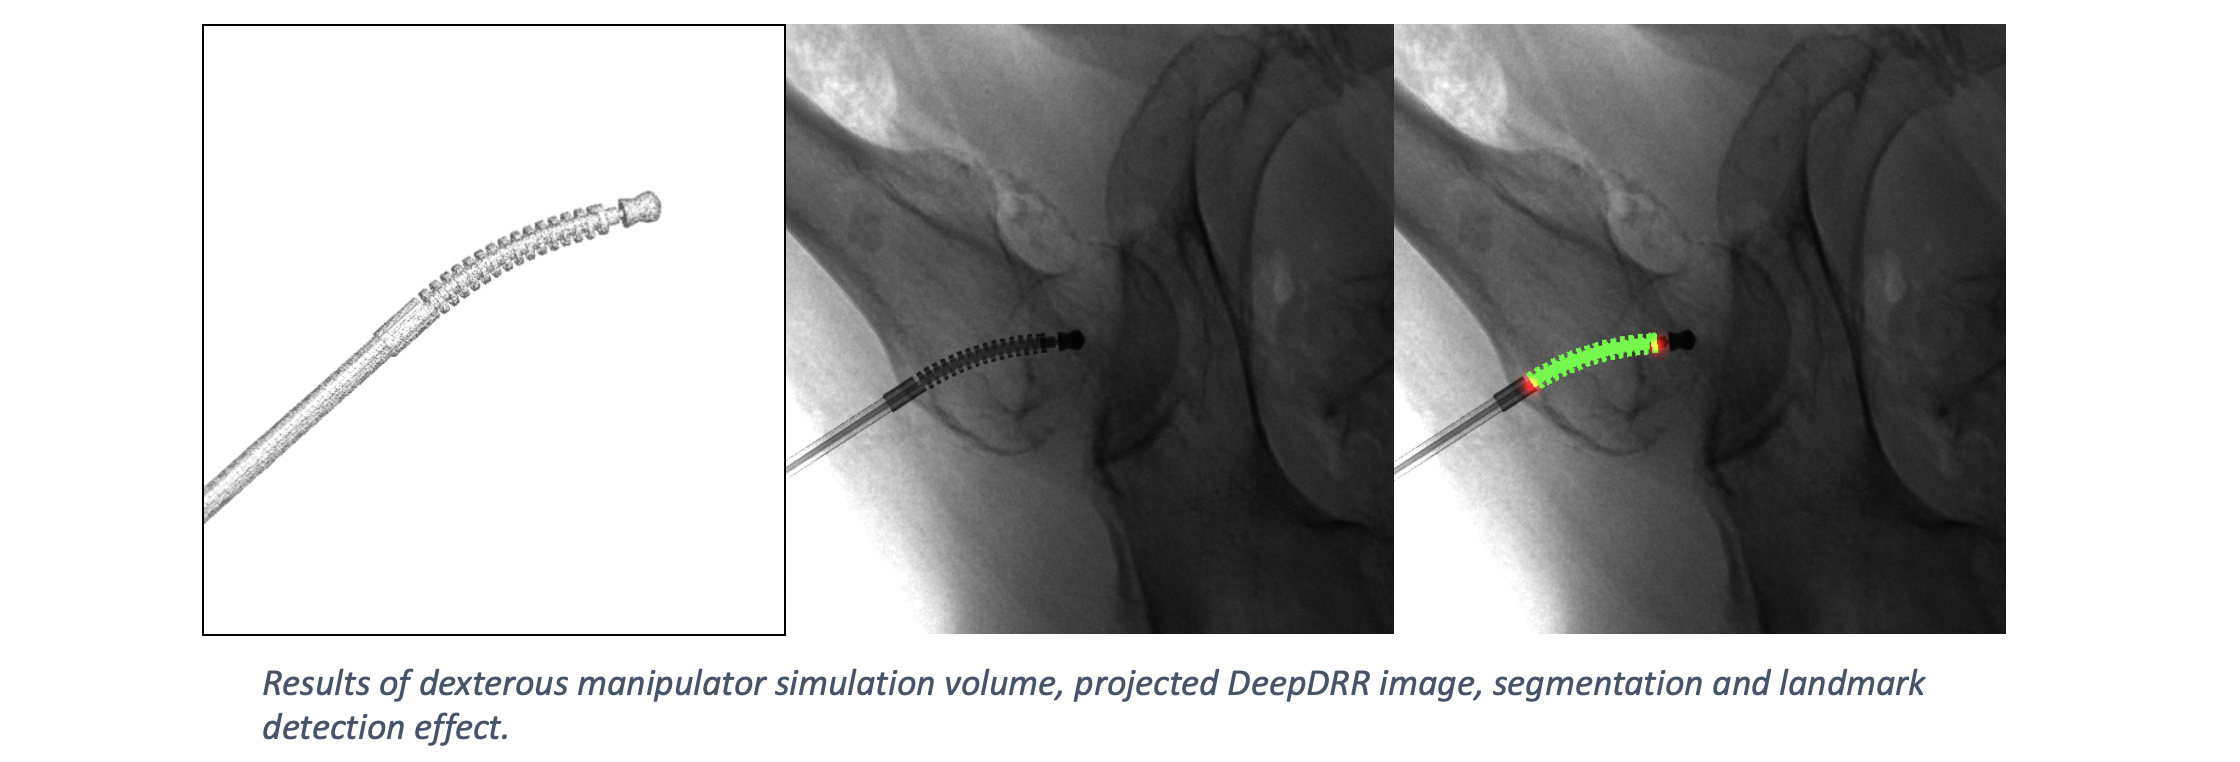

DeepDRR has also been applied to simulate X-rays of the femur during insertion of dexterous manipulaters in orthopedic surgery: "Localizing dexterous surgical tools in X-ray for image-based navigation", which has been accepted at IPCAI'19: https://arxiv.org/abs/1901.06672. Simulated images are used to train a concurrent segmentation and localization network for tool detection. We found consistent performance on both synthetic and real X-rays of ex vivo specimens. The tool model, simulation image and detection results are shown below.

This capability has not been tested in version 1.0. For tool insertion, we recommend working with Version 0.1 for the time being.